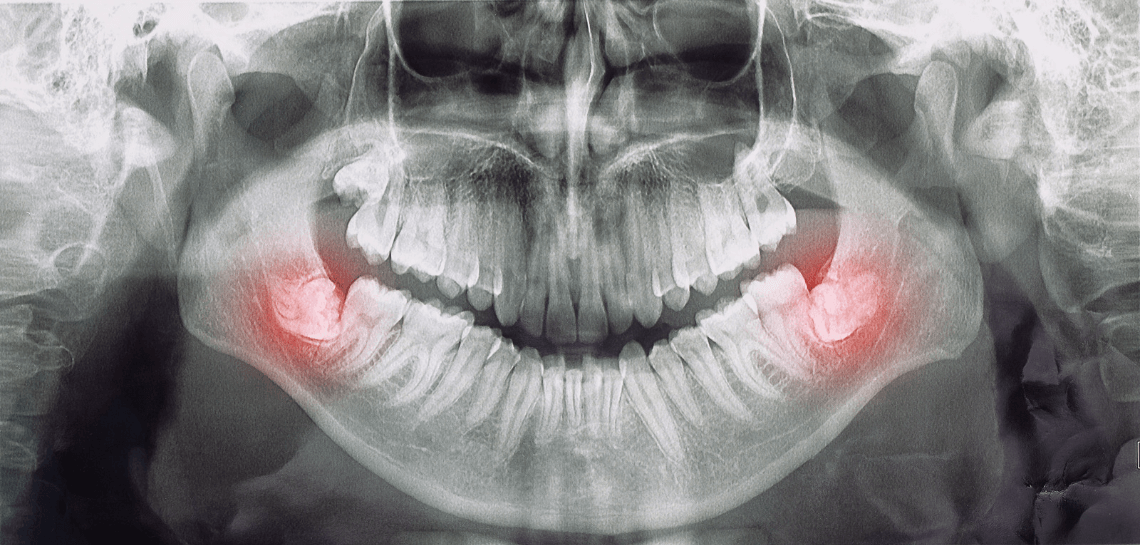

ฟันคุดหรือที่ภาษาอังกฤษเรียกว่า Wisdom Tooth คือฟันที่ฝังอยู่บริเวณใต้เหงือก และไม่สามารถโผล่ออกมาได้ตามปกติเหมือนฟันซี่อื่นๆ หรืออาจจะขึ้นมาได้ไม่เต็มซี่ เนื่องจากมีฟันซี่อื่นขวางอยู่นั่นเอง โดยส่วนใหญ่ฟันคุดมักจะเกิดขึ้นที่บริเวณฟันกรามด้านล่างซี่ที่สาม แต่จริง ๆ แล้วก็สามารถเกิดขึ้นกับฟันซี่บริเวณอื่นได้เช่นกัน

ฟันคุดมีทั้งแบบที่ยังไม่สามารถโผล่พ้นบริเวณของกระดูกขากรรไกรได้ และมีแบบที่พ้นกระดูกขากรรไกรแล้ว แต่ยังไม่สามารถพ้นบริเวณเหงือกออกมาได้ โดยปกติทางการแพทย์เราก็จะต้องทำการผ่าตัดเพื่อเอาออก เนื่องจากเป็นบริเวณที่ทำความสะอาดได้ยากและมักมีเศษอาหารติดอยู่ที่บริเวณช่องว่างระหว่างฟันคุดและฟันซี่ข้างเคียง จนเป็นผลให้เกิดอาการเหงือกอักเสบตามมาได้